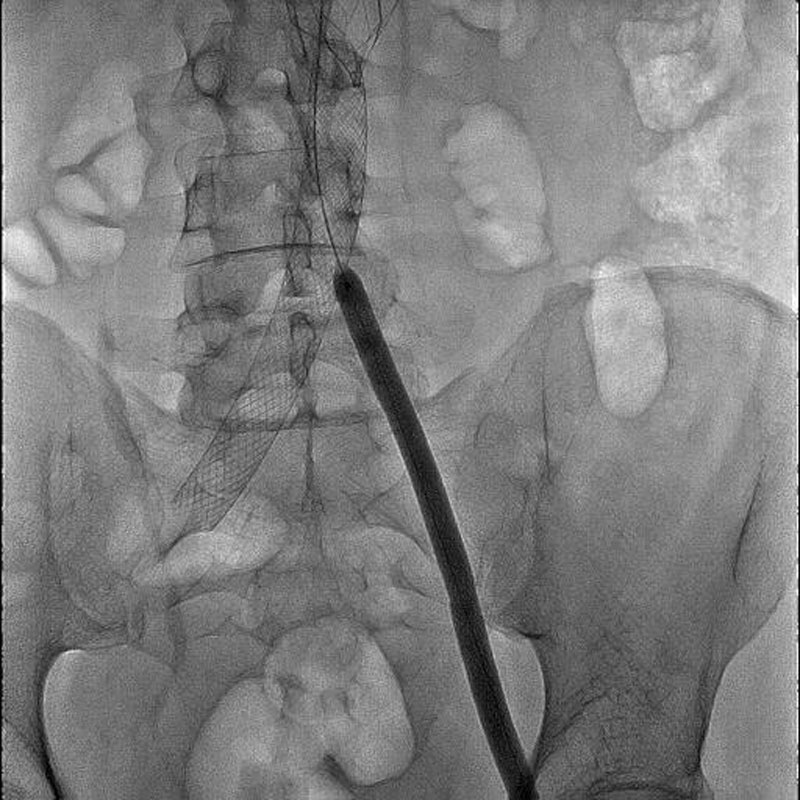

Впервые в России имплантирован венозный стент нового поколения VENOVO, выполнена реканализация и стентирование глубоких подвздошных вен у пациента с синдромом нижней полой вены, развившегося после билатерального илио-феморального тромбоза